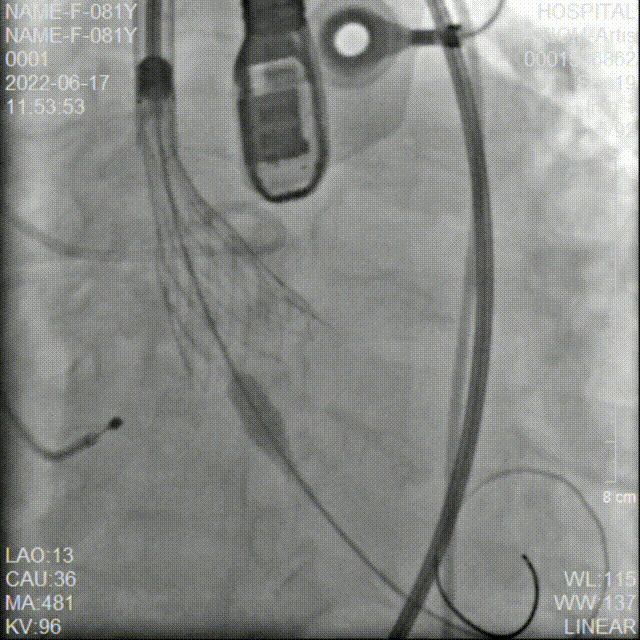

冠脉造影检查

术中20mm球囊预扩可见明显腰征,没有瓣周漏,双侧冠脉灌注情况良好,随后选择AV26瓣膜。TaurusElite AV26瓣膜送至主动脉弓,输送系统轻松过弓及跨瓣。